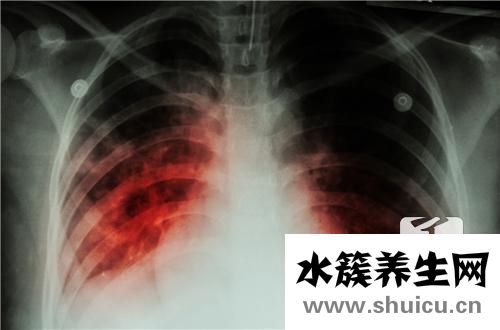

肺結核這類病癥具備極強的感染性,它能夠 根據空氣傳播,會對身邊的人導致十分大的影響,因此 當得了這類病癥以后,一定要嚴加防范,盡量減少病癥的散播。而且在平時的日常生活,要多學習培訓關于肺結核的專業知識,掌握肺結核散播的方式,這針對疾病的治療有十分大的協助。

那麼患肺結核能夠 過夫妻生活嗎?肺結核病人在活躍期,感染性十分的強,能夠 根據呼吸系統及其口水散播,因此 在這個時間范圍以內,千萬別開展夫妻生活,不然那般非常容易造成病況的交叉式感染,進而給醫治導致十分大的困惑。可是假如病人醫治了六個月以上,而且歷經查驗后人體內沒有結核菌的排出來,那麼就可以適當的開展夫妻生活,這個時候病況早已基本獲得控制,不容易再導致病癥的散播。可是干萬不能夠性生活頻繁,不然那般會造成人體抵抗能力越差,進而導致病發癥的產生。

肺結核的防止也十分關鍵。針對肺結核這類病癥而言,最好是的防止方式便是注射卡介苗,那樣能夠 讓人體得到結核菌的抗原體,進而防止結核菌的感染,那樣能夠 大幅度降低患肺結核的概率。此外,也要留意生活起居中的醫護,平常應當搞好防凍保暖的對策,盡量減少發燒感冒受涼,不然那般非常容易造成呼吸系統產生感染,進而導致肺結核的產生。而且還應當積極主動的報名參加鍛煉身體,多開展戶外活動游戲,以提高體質,增強免疫力,這針對預防肺結核的產生也是有十分大的協助。

總得來說,假如病人的肺結核在活躍期,那麼千萬別開展夫妻生活,由于這非常容易造成病癥的散播,乃至還會繼續導致交叉式感染,進而給病況的醫治帶來不利的影響。在平時的日常生活當中,最好是根據注射卡介苗來預防肺結核這類病癥,那樣能夠 大大減少肺結核的感染概率,針對維護的身心健康有十分大的協助。